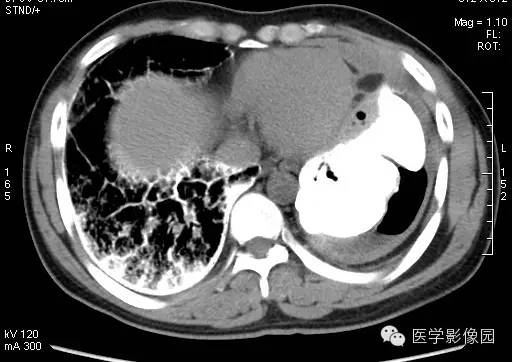

纵隔大细胞神经内分泌癌1例CT影像